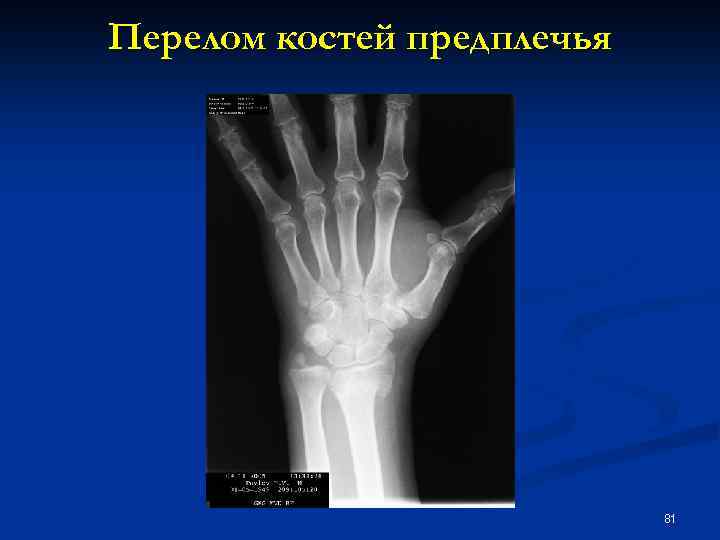

Перелом костей предплечья 81

Частота переломов отдельных костей плечевой кости 2, 2 -7% n предплечья 15, 2 -17, 7% n кисти 5, 4 -8, 9% n бедренной кости 2, 5 -2, 7% n голени 34, 2 -37, 3% n стопы 25 -30% n 68